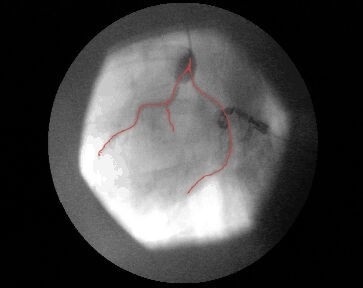

Die Fraunhofer-Technologie-Entwicklungsgruppe TEG in Stuttgart hat den Funktionsnachweis für einen völlig neuartigen diagnostischen Herzkatheter zur indirekten Koronarangiographie und Laevoventrikulographie erbracht. Sein Prinzip beruht auf der Verstärkung des (physiologischen) diastolischen koronaren Blutflusses mit Hilfe eines EKG-getriggerten supraaortalen Ballons und gleichzeitiger Kontrastmittelinjektion in Nähe der Koronarostien [s. Bild 1]. Hierdurch wird über mehrere Herzzyklen eine angiographische Darstellung der Koronararterien erzielt, ohne dass die Koronarostien sondiert werden müssen. Dies führt bei konventioneller Vorgehensweise immer wieder zu Komplikationen. Gefürchtet sind insbesondere die Auslösung von Herzrhythmusstörungen, die Ruptur hauptstammnaher Atherome sowie Gefäßdissektionen.

Als Referenz für die Darstellungsqualität wurden jeweils Koronarangiographien der Herzkranzgefäße in konventioneller Methode von einem Kardiologen durchgeführt [siehe Bild 2]. Es konnte gezeigt werden, dass die neuartige Methode einer indirekten Koronarangiographie in jedem modernen Herzkatheterlabor ohne zusätzliche Investitionen praktikabel ist. In den Versuchen gelang eine überzeugende gleichzeitige Darstellung beider Herzkranzgefäße [siehe Bild 1]. Weiterhin konnte auch die linke Herzkammer in gewohnter Qualität abgebildet werden.